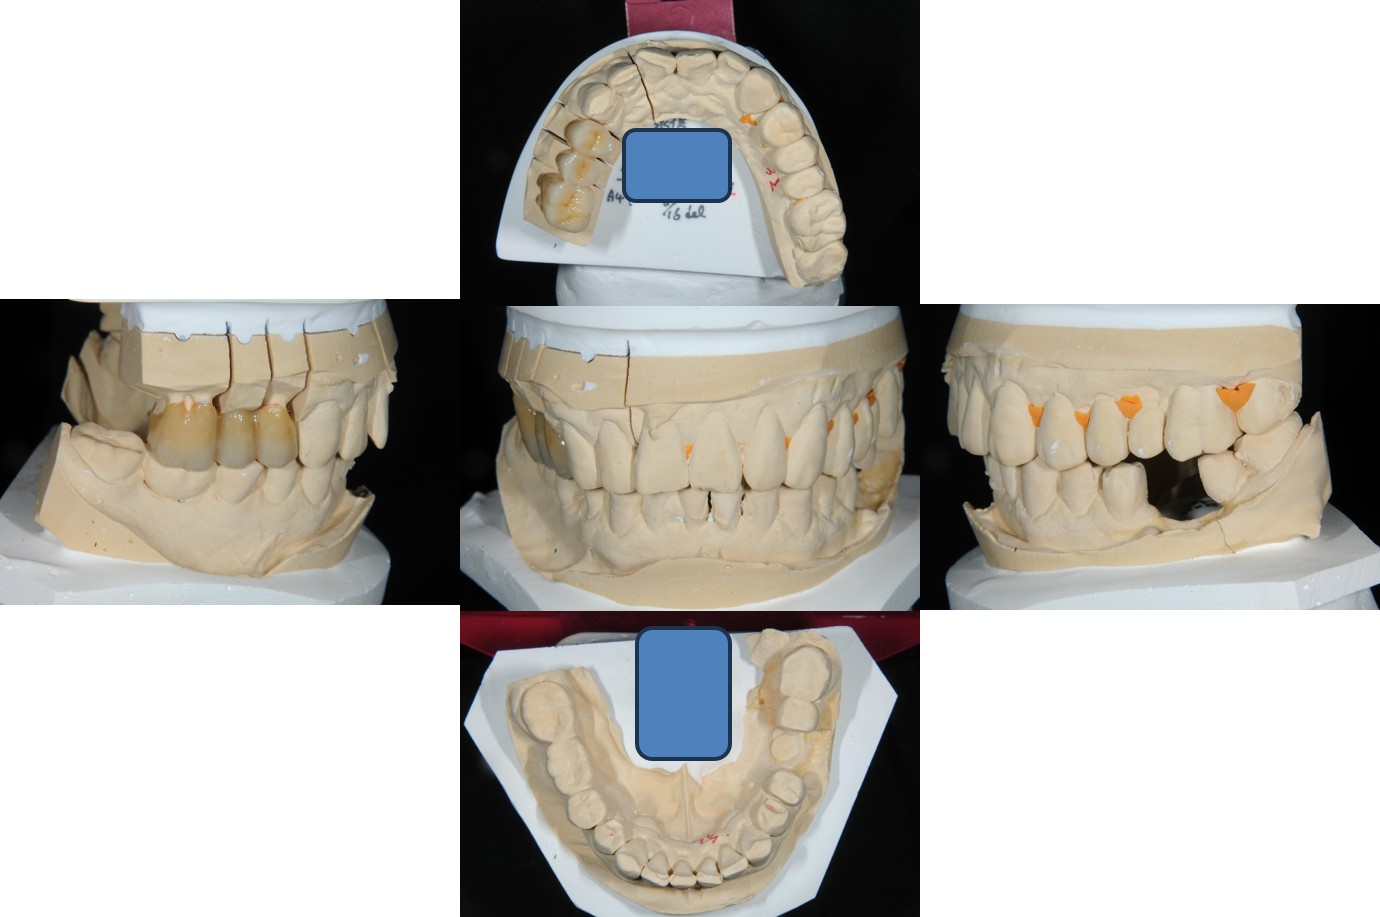

上面弓、上咬合器

技師於咬合器製作全瓷冠